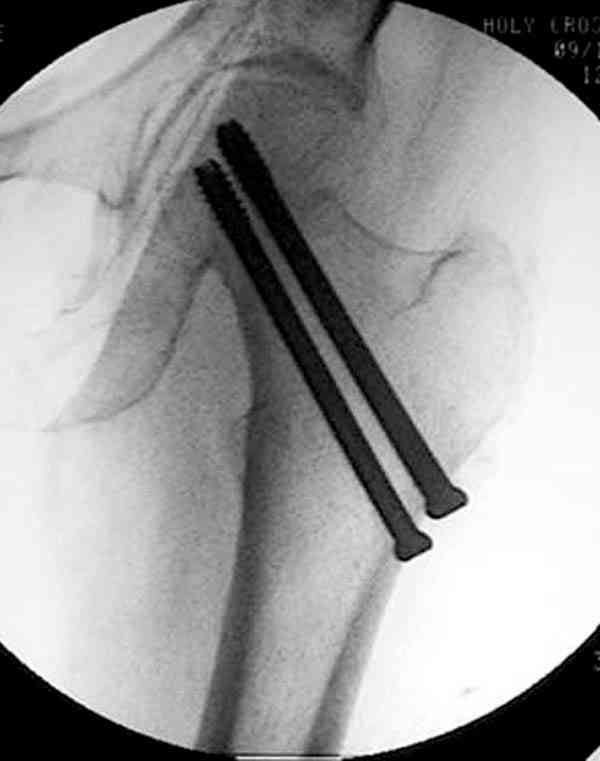

На Московской конференции в ноябре была продемонстрирована удивительная методика профилактического армирования шейки бедра у пациенток с остеопорозом и переломом контрлатеральной шейки в анамнезе.Странно, но дискуссии это сообщение не вызвало.Кто что думает об этом?

Спасибо, Антон. Я автор того сообщения по профилактическому армированию шейки бедренной кости, которое прозвучало на конференции, посвященной 50-летию создания АО. Мне тоже хотелось услышать вопросы по теме. Мы травматологи-ортопеды в первую очередь хирурги, а не терапевты. Почему в вопросе профилактики и лечения остеопороза мы ограничиваемся только консервативными методами лечения? Как можно практически научить больного не получать травмы, когда немало случаев возникновения переломов даже в постели. Первоначально идея армирования ШБК многих, при ком я озвучивал ее, шокировала, затем возникала дискуссия и большинство поддерживали эту идею. Мне бы очень хотелось развернуть дискуссию на странице этого сайта.

Уважаемый Антон! У меня было всего три клинических наблюдения, снимки были продемонстрированы на московской конференции. Количества этих снимков хватило для подачи заявки, а затем и получения патента на изобретение. В свое время РОСПАТЕНТ потребовал подтверждения методики клиническими наблюдениями. У одной из больных действительно произошла повторная травма, и произошел подвертельный перелом на стороне армированной шейки бедренной кости (см. снимки). Это подтвердило основную идею изобретения - была сохранена и головка, и армированная шейка бедренной кости. Но тут не обошлось безпроблем. Анестезиологи отказались давать наркоз, а провести остеосинтез под м/а пластиной и винтом DHS не согласилась больная. Дальнейшее лечение скелетным вытяжением. На контр. Рентгенограмме через 2 месяца признаки формирования костной мозоли. Повторных обращений двух других пациентов не было. Для более детальных исследований и выводов необходимо значительно большее количество клинических наблюдений. Такие исследования могли быть проведены в условиях клиник медуниверситета. Напомню, я работаю в травмотделении провинциальной городской больницы. Насчет экспертов страховых компаний, так пусть они выскажут свое мнение. Армирование кости - это плановые операции по желанию больного, какие здесь могут быть противоречия? На армирование все больные, к моему удивлению, согласились довольно легко и сразу, поэтому остеосинтез и армирование были проведены в течение одной операции. С уважением А.М.

Кстати, очень сомнительна остеопорозность на правом оперированном бедре, отсутствует данные денситометрии с индексом остеопороза.

Коллега Челноков прав, здесь еще имеется риск перелома за счет ослабления латерального кортекса. Во время установки канюлированных шурупов за редким исключением спица вводится с одного раза, множественные попытки ослабляют латеральный кортекс, что станет источником перелома в этом месте.

В идеале для профилактики рефрактуры шурупы надо вводить не больше, чем под 130 градусным углом и не ниже уровня малого вертела.

Насчет биомеханических преимуществ одного шурупа тоже возникает вопрос. Если придерживаться канонов механики, для перелома шейки необходимо 3 паралельных шурупа, расположенных ближе к кортикальному слою шейки.

Здесь случай перелома из-за ослабления латерального кортекса через 3 недели после операции на шейке. Шурупы были установлены под большим углом, слабый латеральный кортекс не выдержал нагрузку.